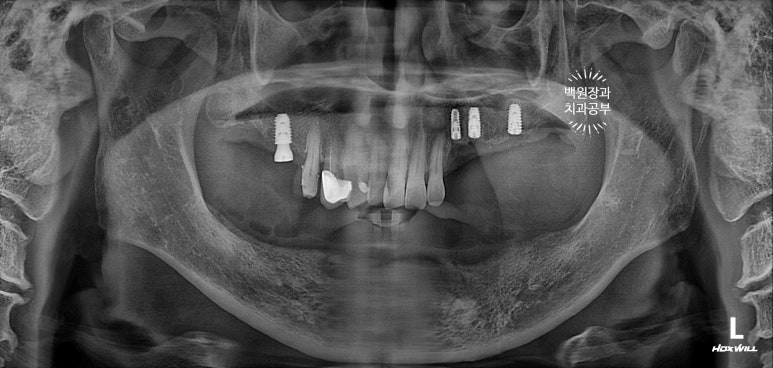

그렇게 오른쪽 1개, 왼쪽 3개의 임플란트를 심어드렸습니다.

제가 자주 포스팅하는 주제 중 하나인 상악동 뼈이식술도 잘 되어있는 것을 확인할 수 있네요~!

바로 이 주황색으로 표시된 부분이 성공적인 상악동 뼈이식술이 진행된 부위입니다.

낙타 봉처럼 둥그렇게 솟아있는 것이 수술이 잘 되었다는 증거입니다. 행여 잘 되지 않는 경우 흐릿하니 그 경계를 파노라마 상에서 확인하기 어렵죠.

아래턱 임플란트 수술을 하였습니다.

아래턱 치아 12개를 만들어드리는데, 6개의 임플란트만 있으면 됩니다.

약 2주 정도 지나서 아래턱 임플란트 6개를 심어드렸습니다.

위턱의 경우 아까 언급하였듯, 임플란트가 심어질 잇몸뼈가 아래턱에 비해 무르기에 보다 많은 임플란트를 필요로 하지만, 아래턱의 경우 전체 임플란트를 위한 최소한의 임플란트 개수는 6개입니다.

송곳니 2개, 작은어금니 2개, 큰어금니 2개 총 6개의 임플란트만 있으면, 아래 완전틀니를 안쓰시게 될 수 있죠.